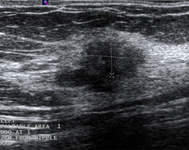

Avaliação de massa mamária

Imagem ultrassonográfica de um carcinoma invasivo

Cortesia do Dr. Lane Roland, Universidade de Louisville; usado com permissão